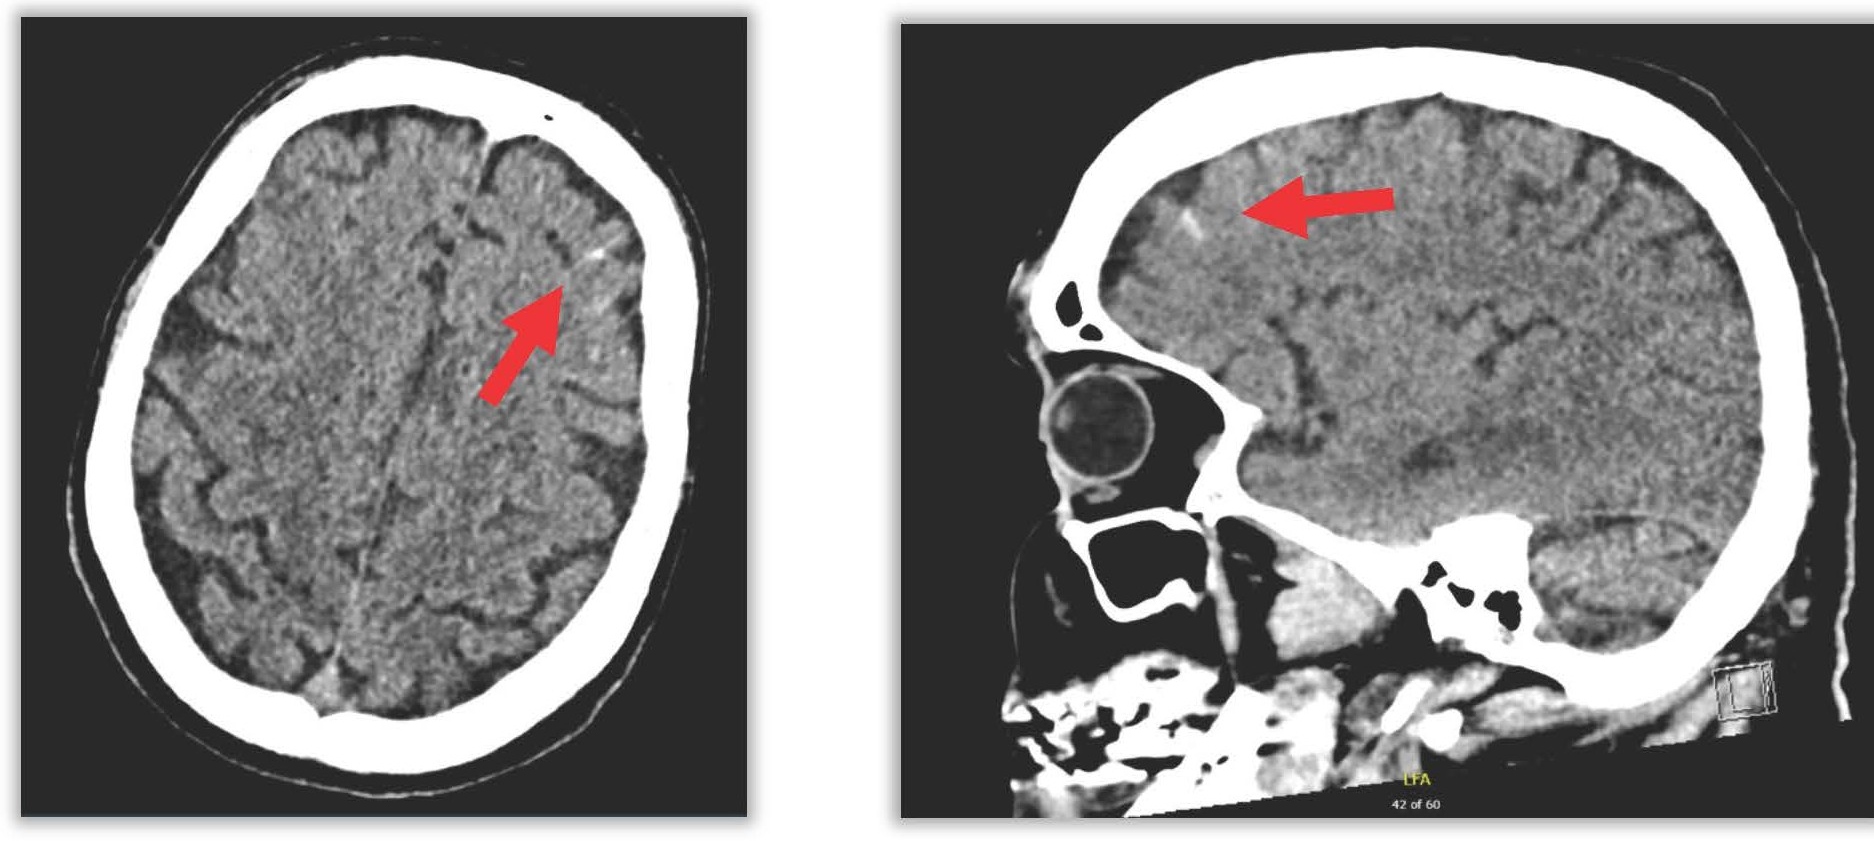

Multidisciplinary discussion led to the suspicion of an atrio-esophageal fistula. Cerebral imaging (CT) showed bilateral subarachnoid hemorrhage in the frontal cortical sulci and hypodense frontal areas likely of ischemic origin (Figure 4).

Figure 4. Subarachnoid frontal hemorrhage.